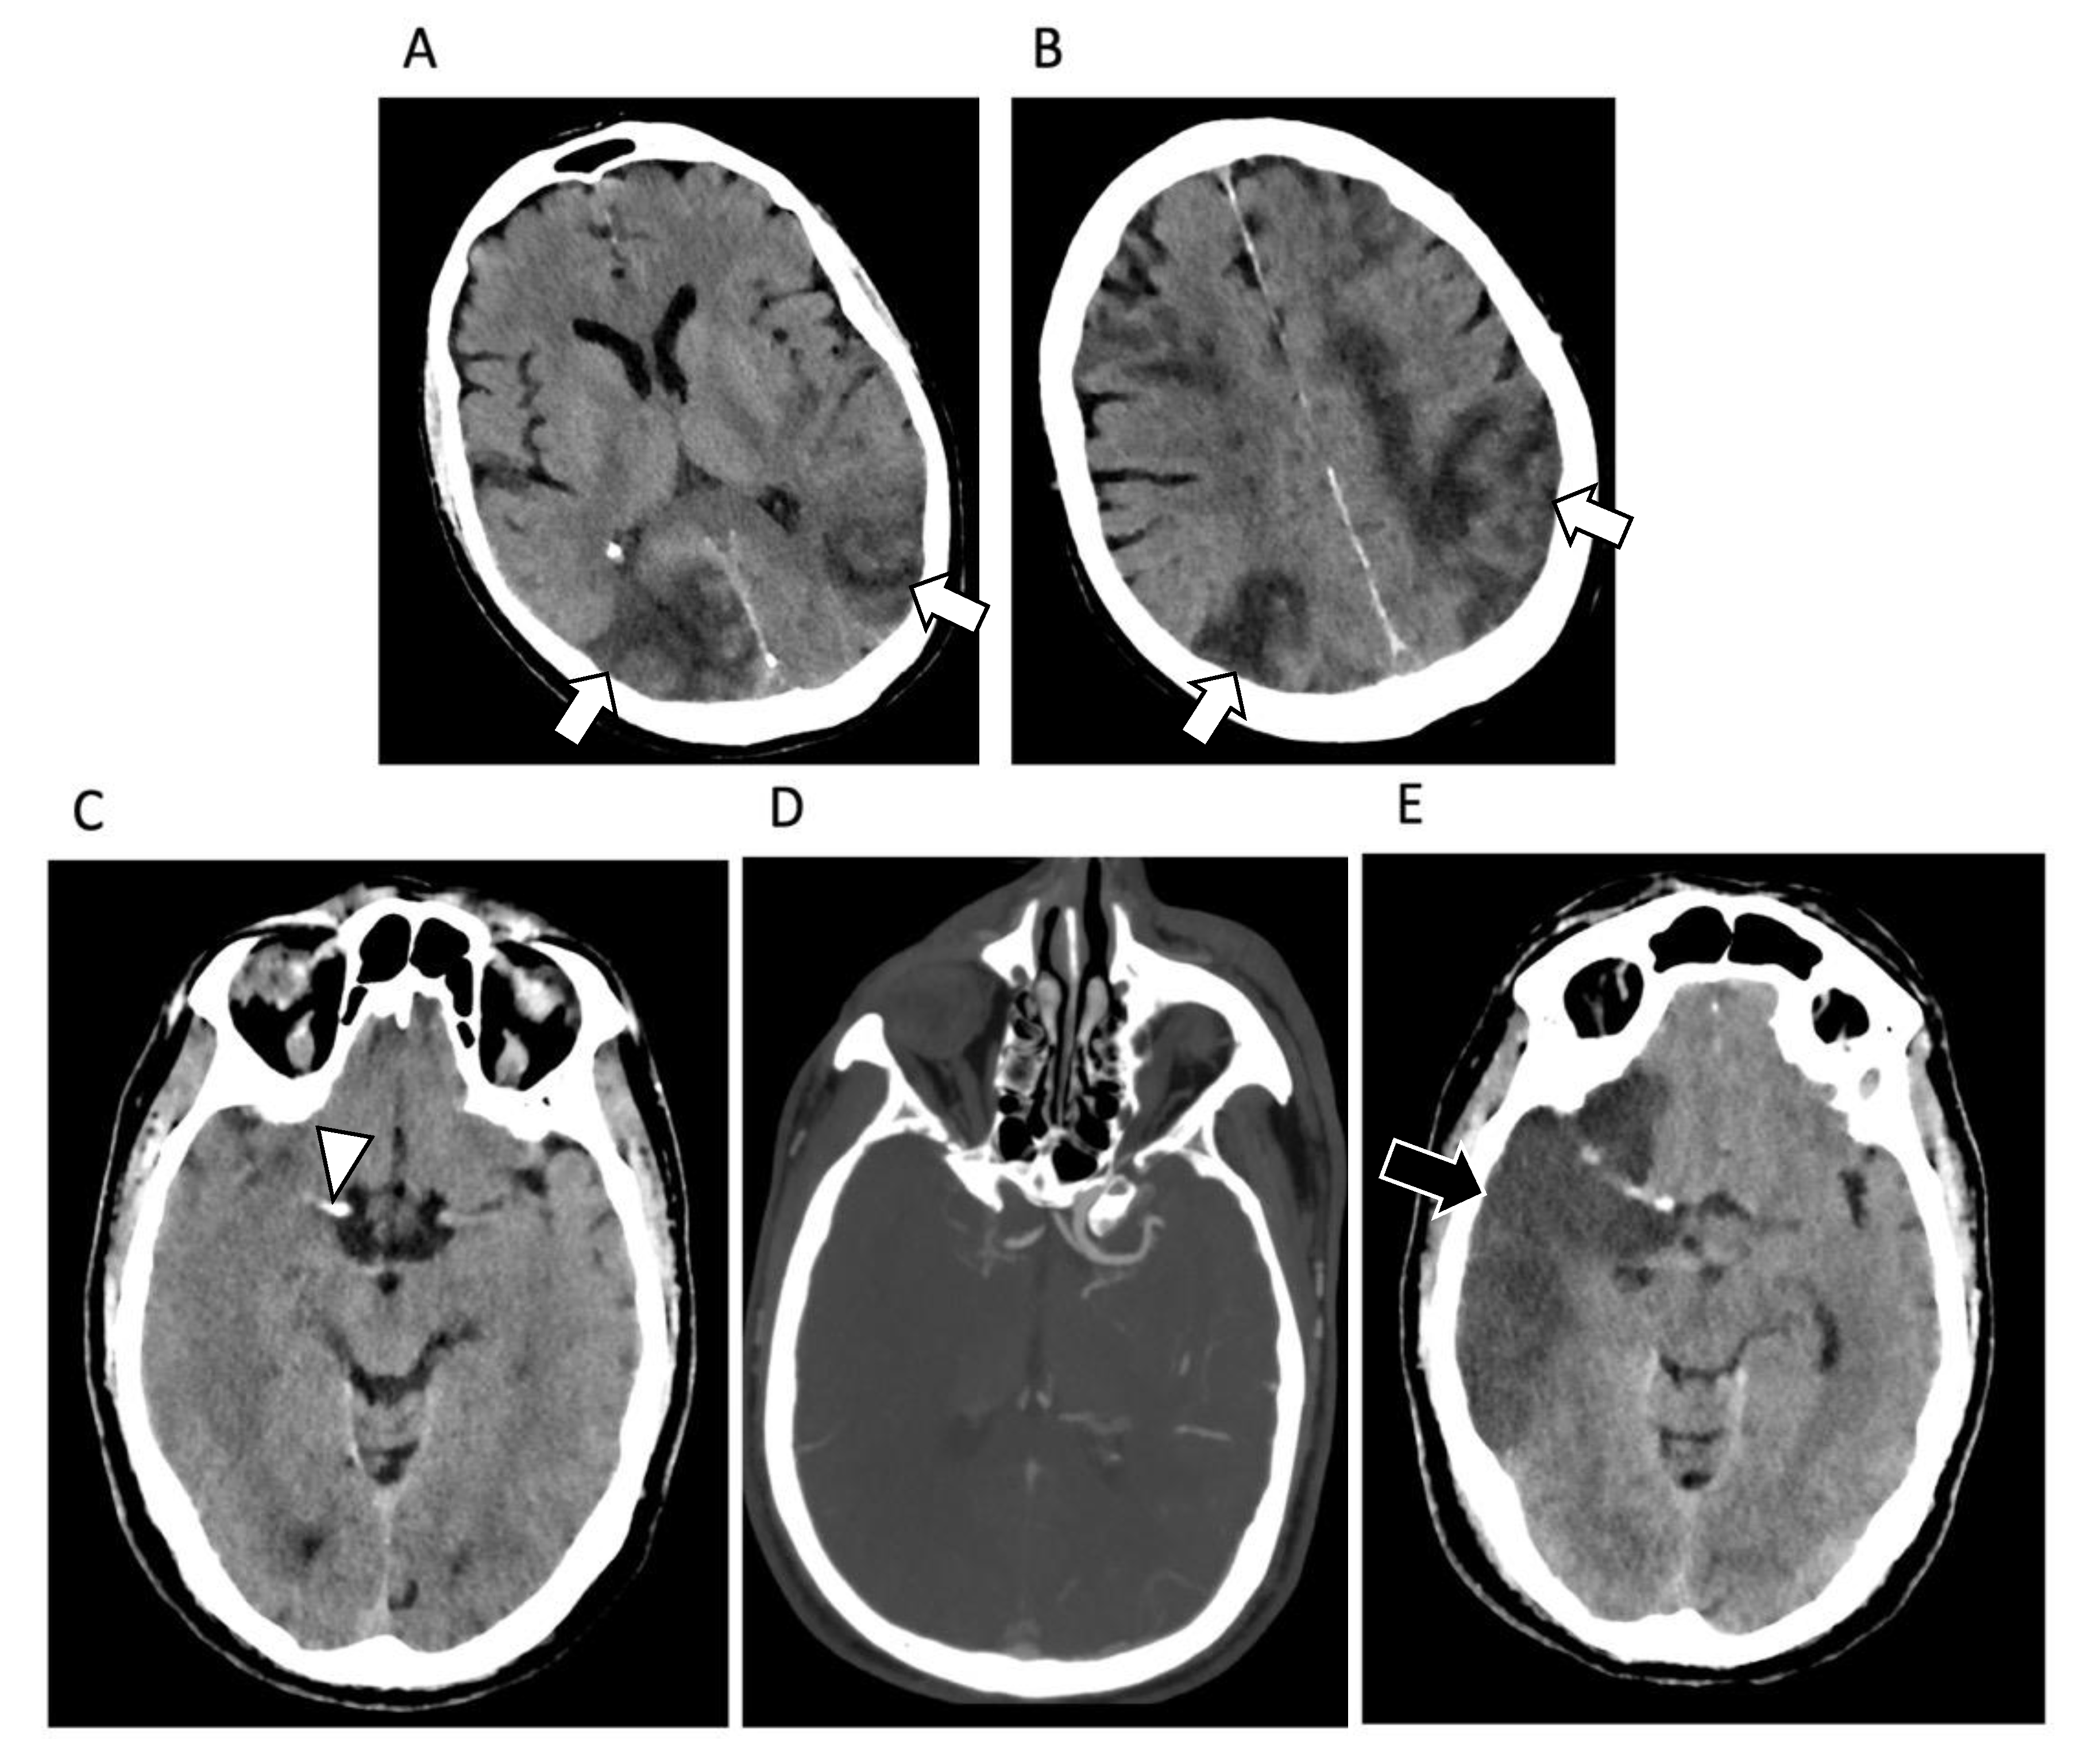

Egbert et al. [63] collected data from 361 patients with COVID neurological symptoms and, in this court, brain abnormalities suggestive of COVID-19 etiology were present in 34%. The most common brain lesions were: white matter (WM) hyperintensities, microhemorrhages, infarct, edema, ischemia, hematoma, and smaller olfactory bulb (Figure 4).

Figure 4.

Brain findings in COVID-19 patients. (A,B) Axial brain CT images of a 56-year-old man affected by SARS-CoV-2-related pneumonia showing multiple hypoattenuating areas located in the cortical junction bilaterally, with a predominant extension in the parietal and occipital lobes, due to ischemia (white arrows). (C) Axial brain CT images of a 71-year-old woman affected by SARS-CoV-2-related pneumonia showing hyperdense artery sign in the right middle cerebral artery (white arrowhead), due to acute thrombosis. This finding was confirmed by brain CT angiography (D) showing a complete thrombosis of the middle cerebral artery. After 15 days brain CT images (E) show a large hypoattenuating area in the fronto-parietal lobe (black arrow) due to the brain ischemia.

WM hyperintensities, which together accounted for 76% of affected cases were bilateral. Changes were also registered in the insular cortex, cingulate gyri, cerebral peduncle and internal capsule and basal ganglia, splenium of the corpus callosum, olfactory nerves/bulb, and gyrus rectus or described as diffuse [64].

Microhemorrhages in WM were noted in about 13% with a bilateral diffuse presentation, in corpus callosum and putamen, bilateral juxtacortical WM, and internal capsule [64]. However, Dixon et al. [65] associate the presence of micro-bleeds in COVID-19 patients with severe hypoxia and not with SARS-CoV-2 neuro-invasion.

Brain stroke was reported in about 10% of cases, mainly with involvement of bilateral anterior and posterior circulation territories. Hemorrhages were noted in about 6% of cases with multiple and various locations, more commonly with bilateral involvement, usually of posterior parieto-occipital lobes and corpus callosum, frontal, occipital, and temporal areas including Sylvian fissure or with lateral ventricles involvement [66,67].